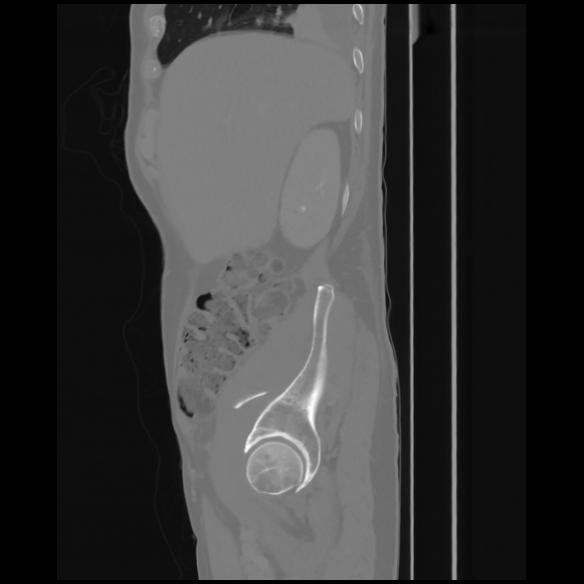

7 CUERPO,CE,Sagittal,3.000,CUERPO,Sagittal,